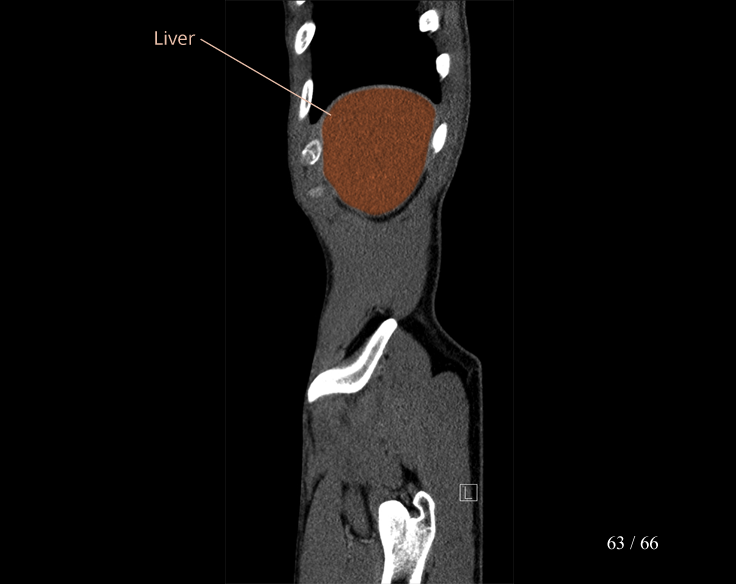

Body

Covers abdominal CT anatomy.